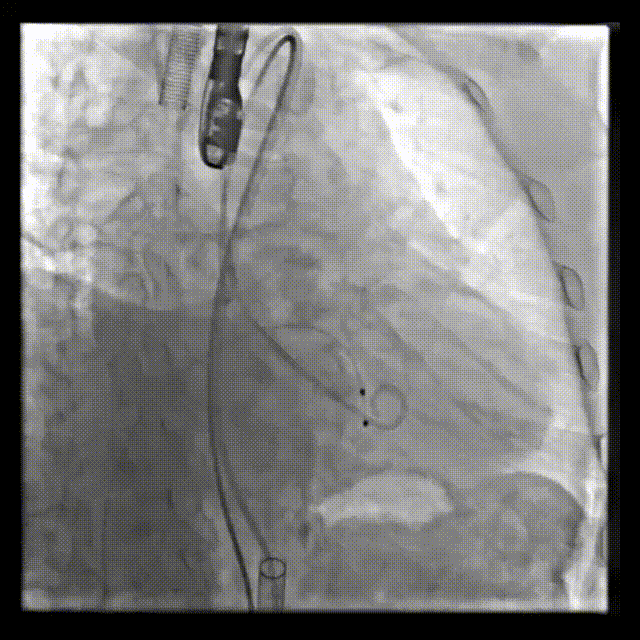

术前造影

术后造影